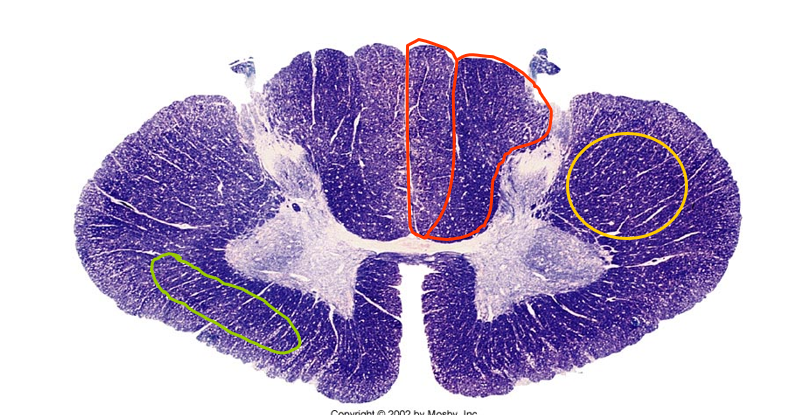

Dorsal column

spinothalamic